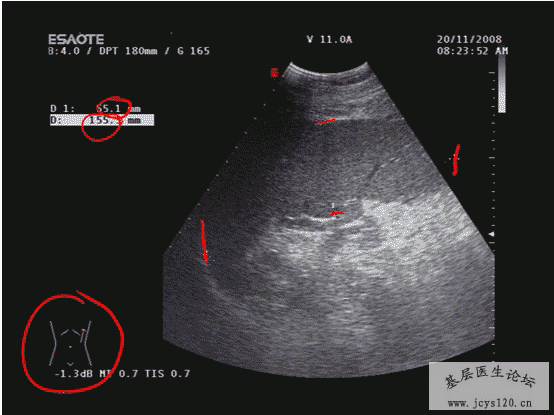

医学教育网讲义里面的精彩图片!